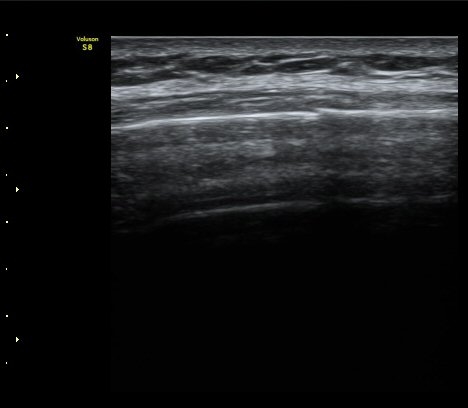

¹Ì¼¼ÇÏ°Ô °¥ºñ»À ÇÇÁú°ñ ¿¬°á¼º ¼Ò½ÇÀÌ °üÂûµÊ(loss of cortical continuity of rib)  »çÁø 1, 2

°¥ºñ»À ¹Ì¼¼°ñÀýÀÌ È®ÀÎ µÊ